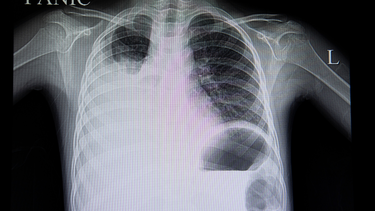

Ung thư phổi sống được bao lâu? Đây là câu hỏi khiến nhiều người lo lắng khi nhận được chẩn đoán mắc bệnh ung thư phổi. Thực tế, tiên lượng sống của bệnh nhân ung thư phổi phụ thuộc vào nhiều yếu tố như giai đoạn phát hiện bệnh, loại ung thư, thể trạng tổng quát, khả năng đáp ứng điều trị và cả tinh thần của người bệnh.

Những năm trước đây, ung thư phổi thường được phát hiện ở giai đoạn muộn, khi khối u đã lan rộng, khiến việc điều trị gặp nhiều khó khăn. Có thời điểm, thống kê cho thấy trong 10 bệnh nhân đến khám hô hấp thì chỉ phát hiện 1 – 2 ca ung thư phổi. Tuy nhiên, hiện nay con số này đã tăng đáng kể, lên đến 5 – 7 trường hợp trong mỗi 10 ca khám. Điều này cho thấy tỷ lệ mắc bệnh ngày càng cao, nhưng cũng đồng thời phản ánh sự cải thiện trong công tác tầm soát và chẩn đoán sớm.

Khi bệnh được phát hiện ở giai đoạn đầu, cơ hội kéo dài tuổi thọ và nâng cao chất lượng sống của bệnh nhân sẽ cao hơn rất nhiều. Nhờ sự phát triển mạnh mẽ của y học hiện đại, các phương pháp điều trị như phẫu thuật, hóa trị, xạ trị, điều trị trúng đích và liệu pháp miễn dịch đã giúp cải thiện đáng kể tiên lượng sống cho người bệnh. Có những bệnh nhân ung thư phổi đã sống thêm nhiều năm, thậm chí trên 5 năm, nếu được điều trị tích cực và đúng phác đồ.

Tuy nhiên, với các trường hợp phát hiện muộn, tiên lượng sống thường không cao. Nhiều bệnh nhân chỉ có thể sống thêm vài tháng, thậm chí dưới một năm nếu ung thư đã di căn rộng. Nhưng điều này không đồng nghĩa với việc buông xuôi. Bằng cách kết hợp điều trị y học và chăm sóc toàn diện cả thể chất lẫn tinh thần, người bệnh vẫn có thể kéo dài thời gian sống và nâng cao chất lượng cuộc sống trong thời gian còn lại.